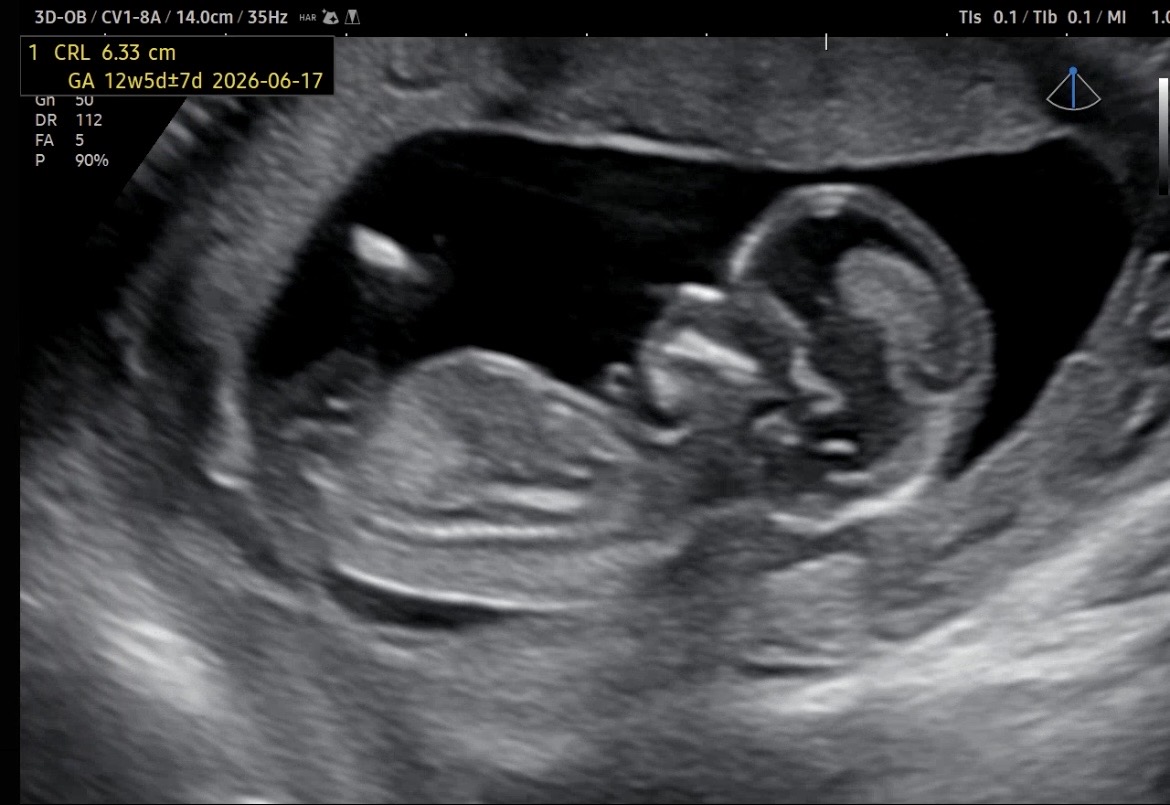

12주 4일차입니다 투표해주세용🥰